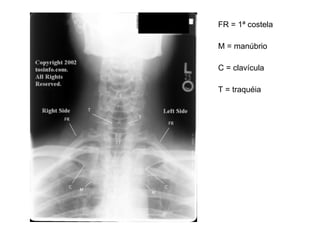

FR = 1ª costela M = manúbrio C = clavícula T = traquéia

FR = 1ªcostela M = manúbrio C = clavícula T = traquéia